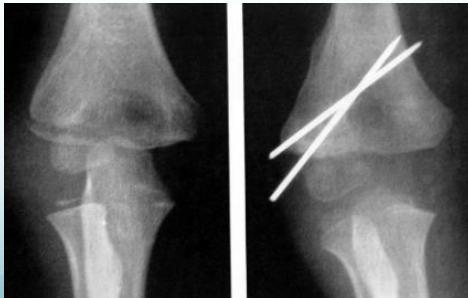

Displaced fractures:

- Closed reduction and fixation with K-wires & slab

Case Example: 6-year-old girl, fell from swing

Lateral Condyle - Humerus

- Treatment: reduction, K-wire, slab